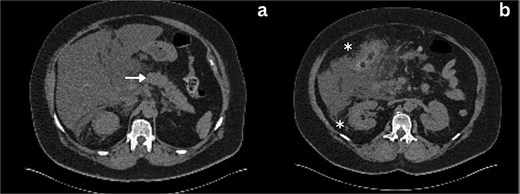

She was admitted, resuscitated, and started on intravenous antibiotics. Considering her previous history of cholecystectomy and deranged Liver Function Tests (LFTs), a clinical diagnosis of cholangitis was made. Magnetic retrograde cholangio-pancreatography (MRCP) was done, which showed significant dilatation of the biliary system extending down to the ampulla with the common hepatic duct (CHD) diameter of 23 mm with a normal pancreatic duct. Additionally, there was florid upper abdominal edema and fluid tracking along the right paracolic gutter (Fig. 1). There was no evidence of any common bile duct (CBD) stone or lesion to explain this dilatation. To further explore the underlying cause, a computed tomography (CT) pancreas was performed, which revealed no signs of pancreatitis nor any distal CBD or pancreatic lesions. The presence of fluid in the subhepatic and right paracolic regions likely indicated a bile leak (Fig. 2), but fluid related to pancreatitis could not be excluded. The findings were deliberated upon with the specialist hepatopancreaticobiliary (HPB) team and Specialist gastrointestinal (GI) radiologists. Despite extensive discussion and review with the radiologist, the nature of the fluid was not identified through the two imaging modalities employed. There was no obvious pancreatitis. A decision was reached to continue conservative management and opt for operative intervention in the event of clinical deterioration.

Axial section CT imaging; a) Normal pancreas with no evidence of inflammation or malignancy (arrow), b) extrahepatic biliary collection (asterisks).